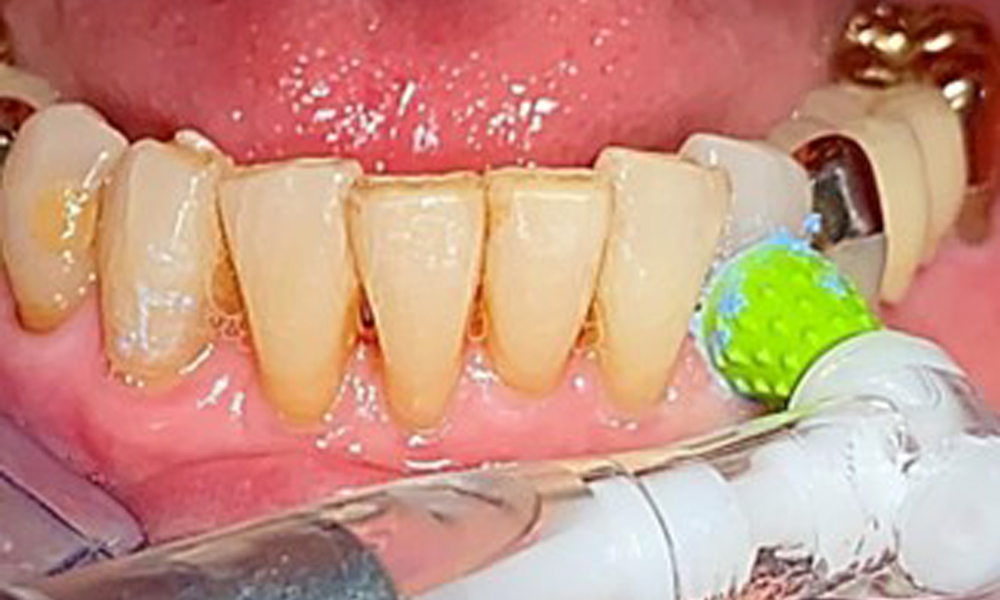

The patient was fitted with a combined removable maxillary telescopic prosthesis more than 25 years ago (Fig. 1, Fig. 2, Fig. 3) and is very happy with her dentures. The patient has an adequate fixed denture for the mandible (Fig. 4).

The dental findings are as follows: Combined removable implant and tooth-supported telescopic prostheses on implants 15, 13, 21, 23, 24, 25 and tooth 11 (Fig. 1, Fig. 2, Fig. 3). The patient was fitted with a fixed mandibular denture. Adequate bridges were present over 37 to 34 and 45 to 47 (Fig. 4), the crown margins were intact and there were no active caries. A composite filling with a marginal gap was present on tooth 43. There was mandibular gingival recession, exposing 1 to 3 mm of root surface. This also applies to 11.

Occlusal view of the mandible.

Fig. 4: Occlusal view of the mandible.